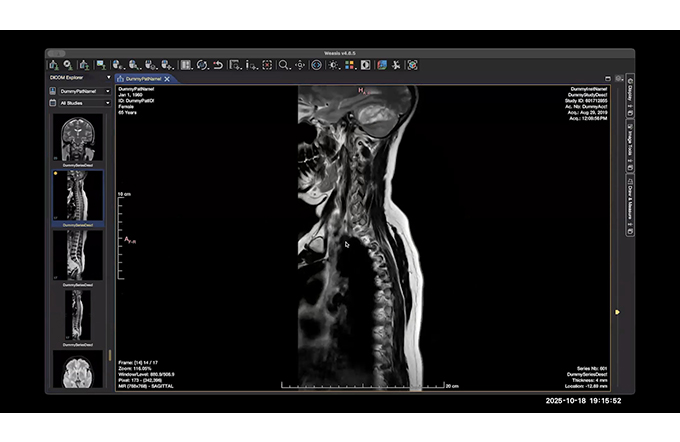

Neuro - Only Cases

RWRW Webinar

radiology